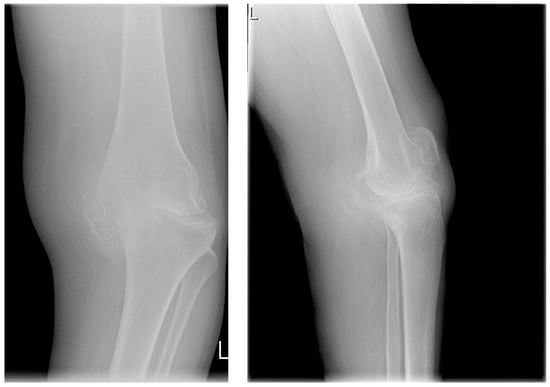

The patients underwent radiological assessment in accordance with generally accepted standards of radiological diagnostics. Based on the radiographs taken in the anterior–posterior and lateral positions, the severity of the osteoarthritis was determined on the Kellgren–Lawrence scales (Figure 3). On the first scale, patients were assigned to the appropriate degree of osteoarthritis, from grade 0 to 4.

Figure 3. Radiographs of the knee joint. Grade-4 arthrosis on the K–L scale, grade 3 on the Crofty-Lane scale. Left—AP view, right—lateral view. Visible (yellow arrow) complete narrowing of the joint space in the medial compartment, numerous osteophytes (blue arrows), and joint-axis disorders. Upper part: femoral bone, lower part: tibia and fibula. Source: proprietary material.